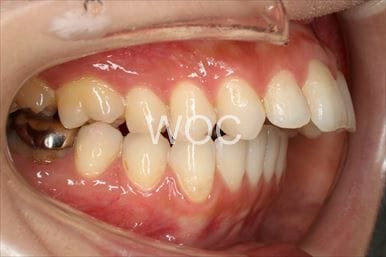

治療中1

治療中2

治療中3

治療中4

治療中5

- 年齢:17歳女性

- 主訴:出っ歯、前歯のガタガタが気になる

- 基本矯正料金:78万円

- 治療期間:1年2ヶ月

- 抜歯部位:上顎両側第一小臼歯